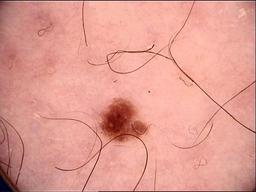

Skin lesion datasets provide essential information for understanding various skin conditions and developing effective diagnostic tools. They aid the artificial intelligence-based early detection of skin cancer, facilitate treatment planning, and contribute to medical education and research. Published large datasets have partially coverage the subclassifications of the skin lesions. This limitation highlights the need for more expansive and varied datasets to reduce false predictions and help improve the failure analysis for skin lesions. This study presents a diverse dataset comprising 12,345 dermatoscopic images with 40 subclasses of skin lesions, collected in Turkiye, which comprises different skin types in the transition zone between Europe and Asia. Each subgroup contains high-resolution images and expert annotations, providing a strong and reliable basis for future research. The detailed analysis of each subgroup provided in this study facilitates targeted research endeavors and enhances the depth of understanding regarding the skin lesions. This dataset distinguishes itself through a diverse structure with its 5 super classes, 15 main classes, 40 subclasses and 12,345 high-resolution dermatoscopic images.